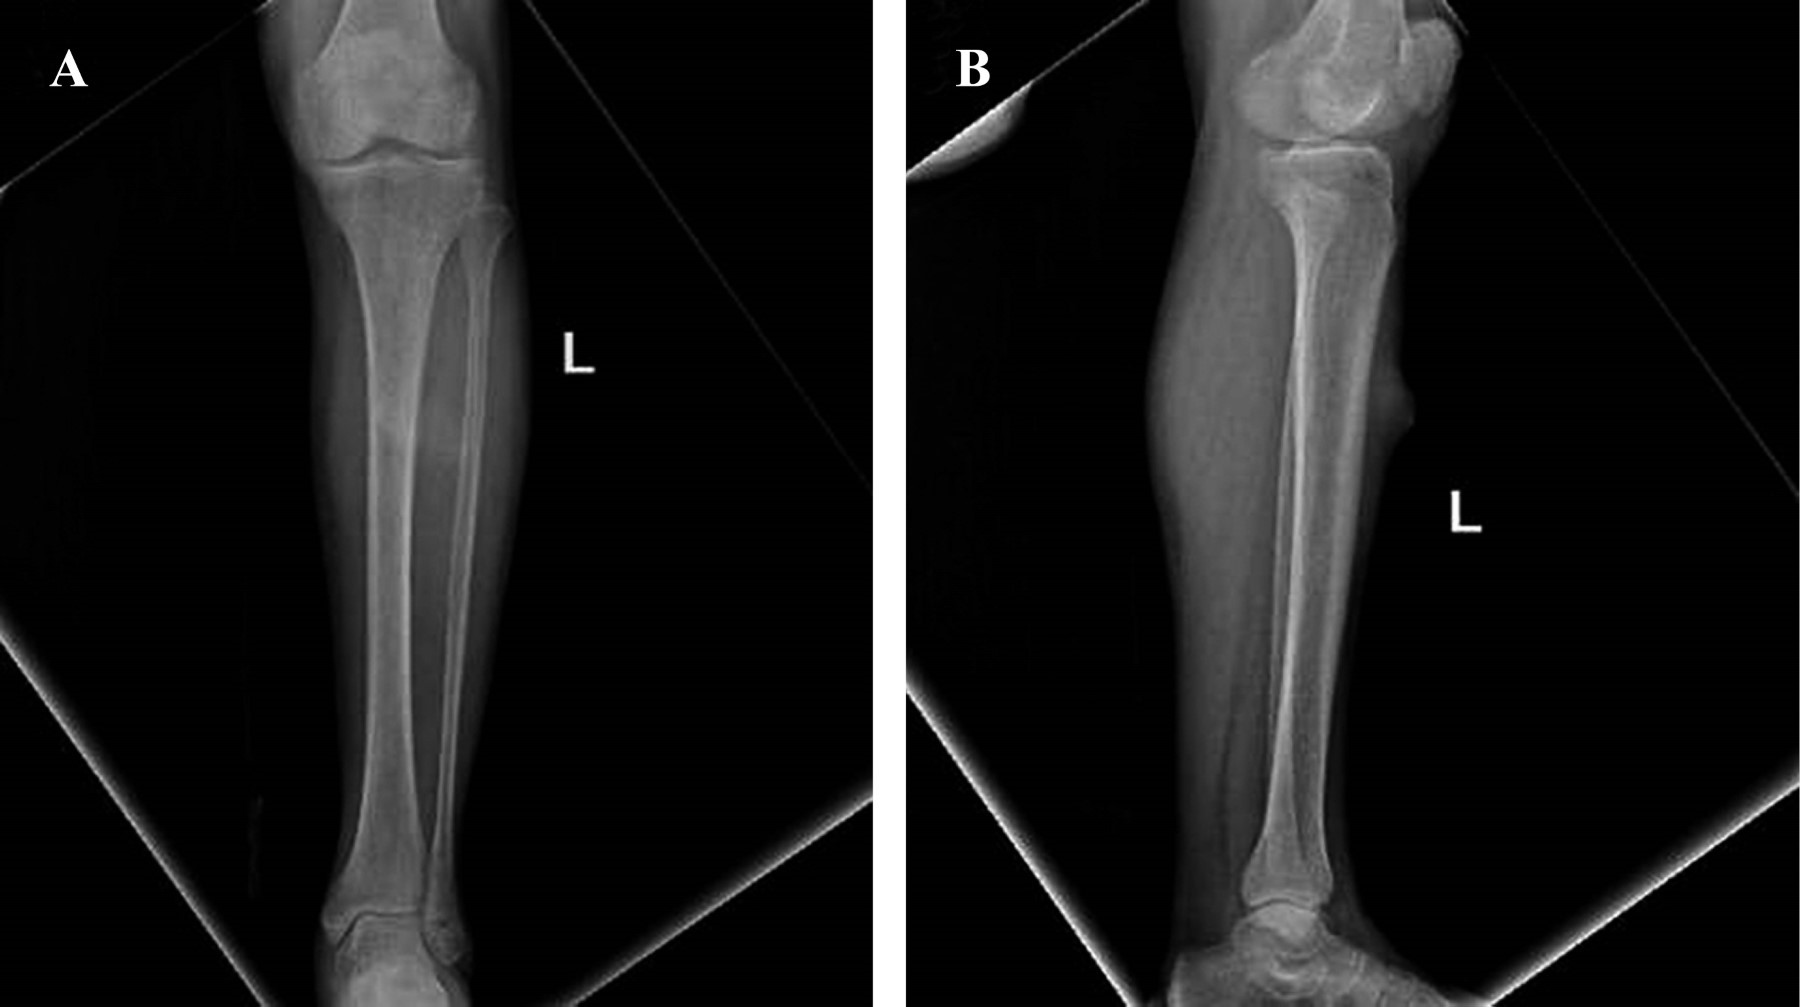

Las radiografías simples mostraron aumento de volumen en tejidos blandos y una lesión radiopaca en región proximal de pierna izquierda (Figura 2). En las imágenes de resonancia magnética se encontró una lesión nodular localizada en piel y tejido celular subcutáneo de la cara anterior del tercio proximal de la pierna izquierda con bordes parcialmente delimitados, lobulados con edema de tejidos blandos adyacentes sin compromiso de la fascia muscular, de comportamiento hipointenso en T1 e hiper/isointenso en T2 y T2 FAT-SAT, con comportamiento heterogéneo de aproximadamente 26 × 27 × 17 mm (Figura 3).

La paciente mostró una evolución favorable, logrando una adecuada integración del injerto y recuperando movilidad total. Se programaron radiografías de seguimiento, las cuales inicialmente no mostraron anormalidades; sin embargo, cuatro meses posteriores a la resección, la paciente experimentó dolor en la zona previamente afectada y nuevas radiografías mostraron una persistencia local en la pierna izquierda. Se discutió con la paciente la necesidad de una nueva intervención quirúrgica aunado a tratamiento con radioterapia, finalmente la paciente decidió no aceptar el tratamiento. Ante su decisión, se optó por continuar solamente con vigilancia de la lesión.

El sarcoma fibroblástico mixoinflamatorio muestra características inespecíficas en la resonancia magnética debido a su amplia variabilidad histológica, lo que puede afectar su apariencia en los estudios de imagen.16 Sin embargo, en nuestro caso, los hallazgos imagenológicos son consistentes con los descritos en otros casos reportados.2,3,4,11,14 En cuanto a las características histológicas, éstas también resultaron concordantes con la mayoría de los casos recopilados en nuestra revisión,2,3,4,5,9,10,11,16 a excepción del caso reportado por Boran y colaboradores, el cual presentó necrosis por coagulación, así como proliferación fibroblástica en el tejido óseo.15